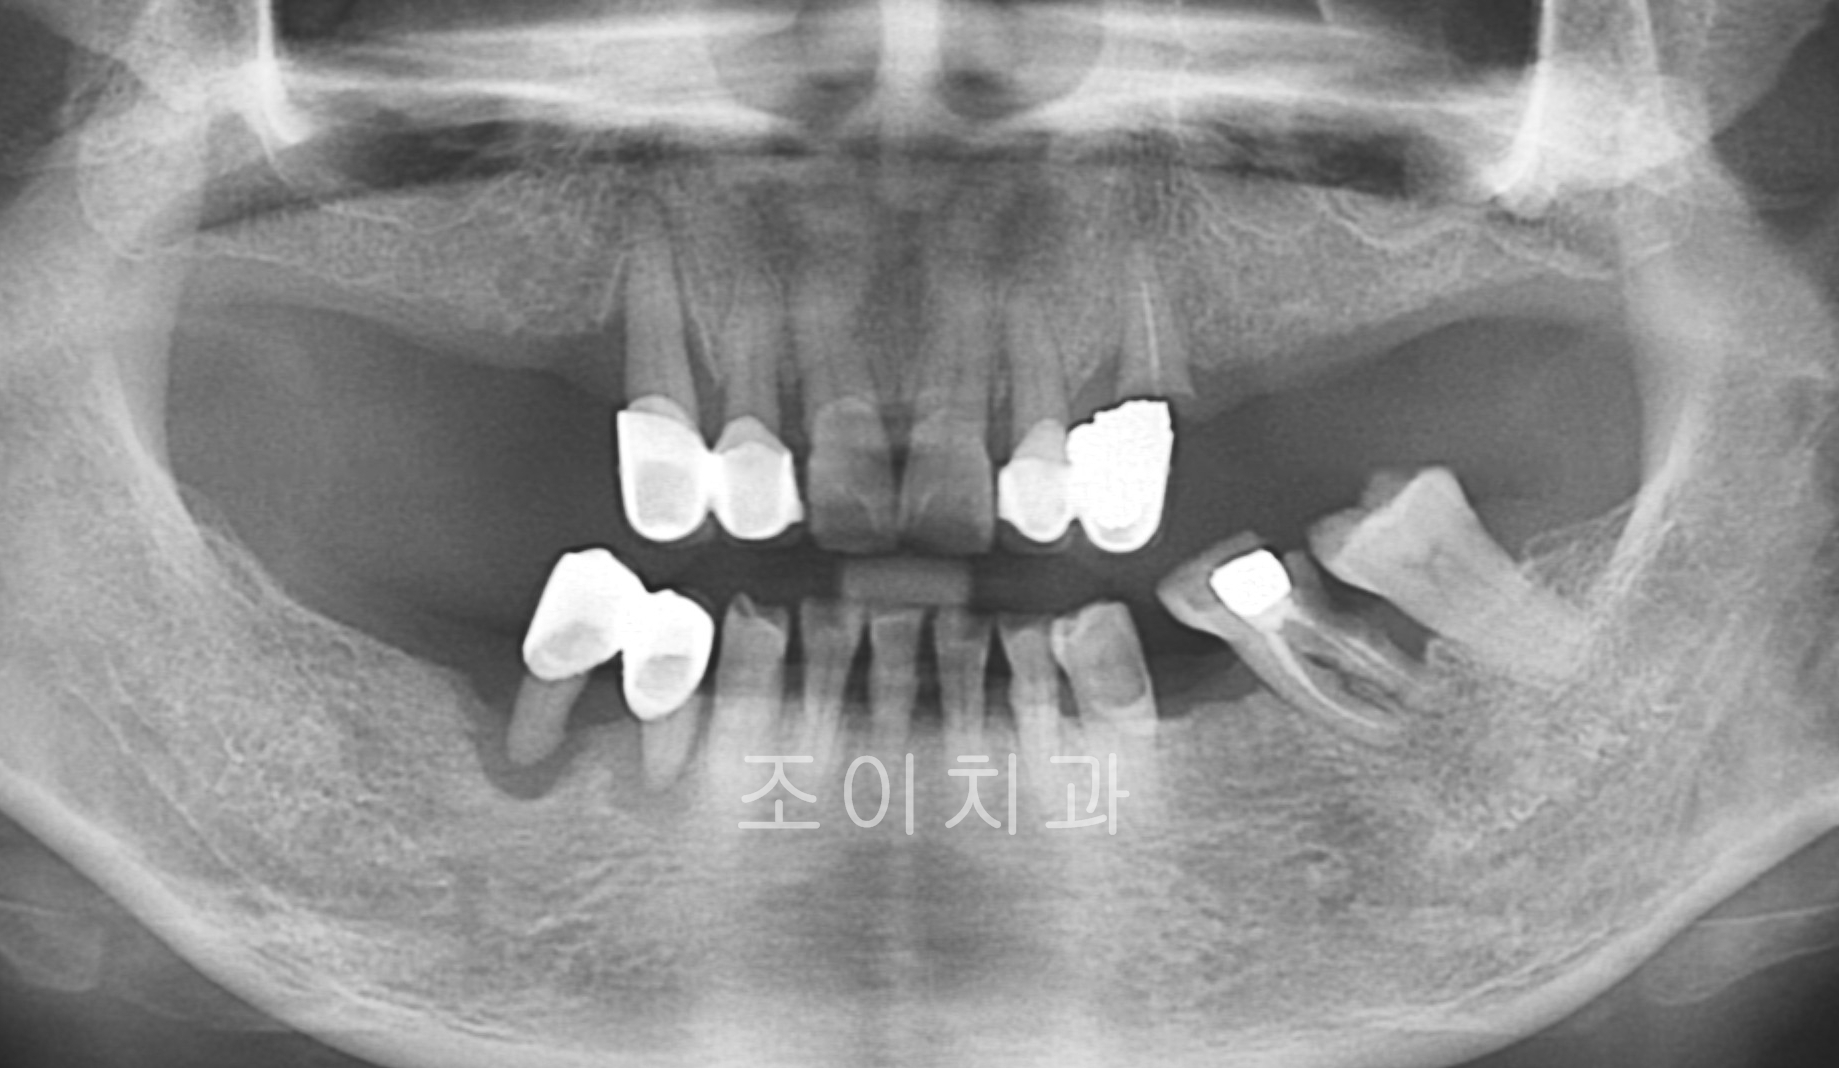

[임플란트] 제목 : 상악 전악 및 하악 구치부

x-ray